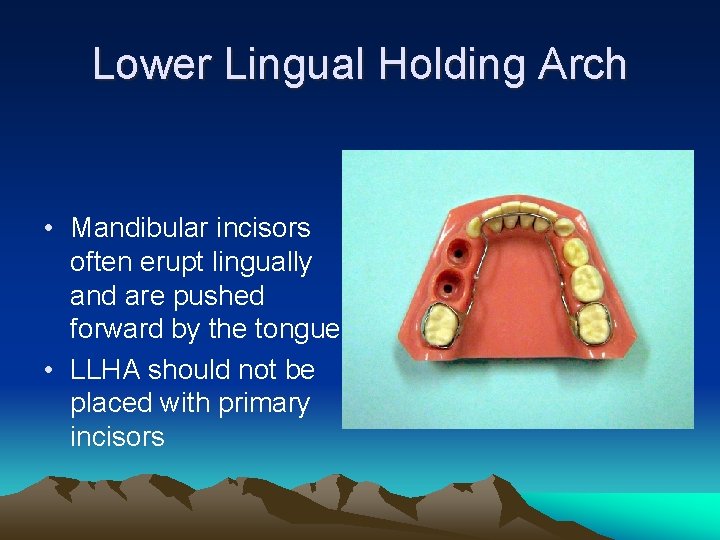

Lower Lingual Holding Arch • Mandibular incisors often erupt lingually and are pushed forward by the tongue • LLHA should not be placed with primary incisors